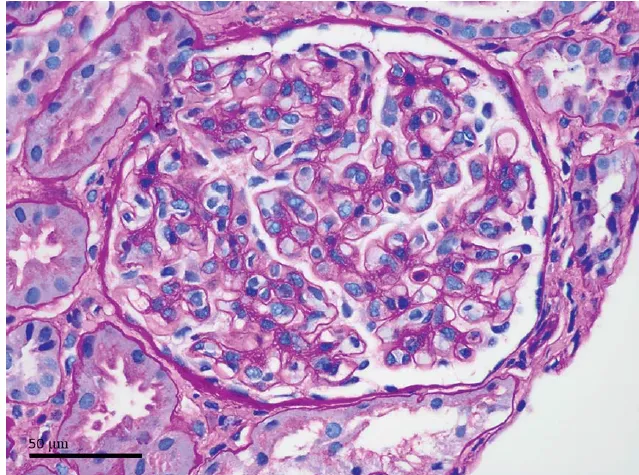

Qual é o significado do edema da medula óssea na ressonância magnética?

A RM revelou edema da medula óssea próxima à superfície externa da articulação do tornozelo da tíbia e

tálus, com leve coleção de líquido periarticular. Não foram observadas evidências de necrose óssea avascular ou lesão traumática. O edema na região medular óssea pode ser observado em condições como osteoartrite, onde a

cartilagem está danificada. Em casos de artrite reumatoide, o edema medular ósseo pode preceder o desenvolvimento de erosões ósseas. Na espondilite anquilosante, o edema pode anteceder o desenvolvimento da calcificação na inserção do tendão.

No caso presente, o diagnóstico de CIPS foi estabelecido após a exclusão de outras causas de edema da medula

óssea e a ausência de evidências de distrofia simpática reflexa, artrite inflamatória ou osteoporose.